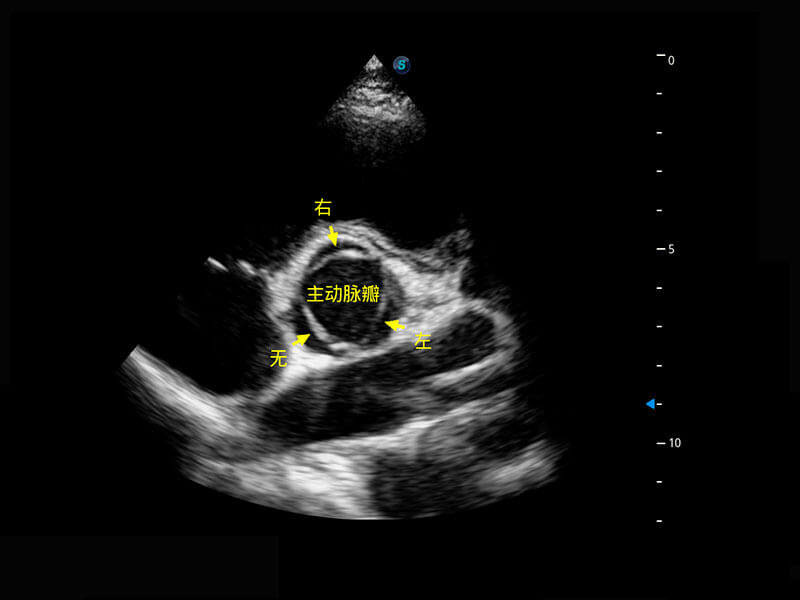

胎心筛查

P60搭载一系列胎儿心脏成像技术,实现更精细的胎儿心脏评估。

• 四腔切面

• 四腔心血流

• 右室双出口

• 胎心容积成像